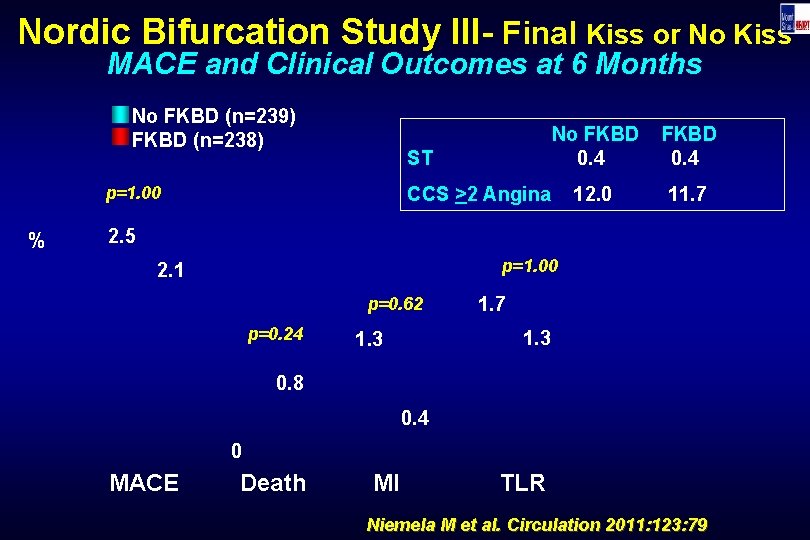

Nordic Bifurcation Study III- Final Kiss or No Kiss MACE and Clinical Outcomes at 6 Months No FKBD (n=239) FKBD (n=238) ST p=1. 00 % No FKBD 0. 4 12. 0 11. 7 CCS >2 Angina 2. 5 p=1. 00 2. 1 p=0. 62 p=0. 24 1. 7 1. 3 0. 8 0. 4 0 MACE Death MI TLR Niemela M et al. Circulation 2011: 123: 79